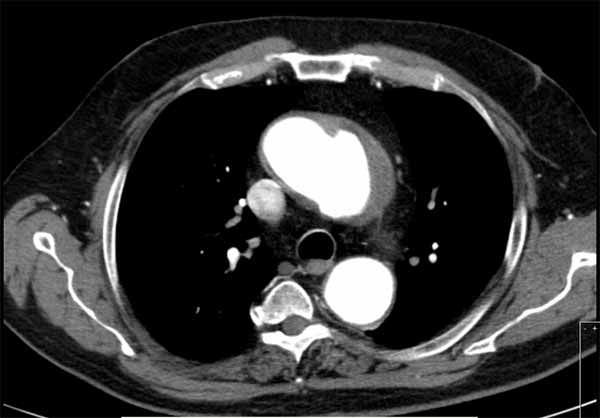

Aortic aneurysm with extensive mural thrombus. Transverse scan: thrombus appears as heterogeneous image that partially fills the aneurysm. if you want to kno ... View Video